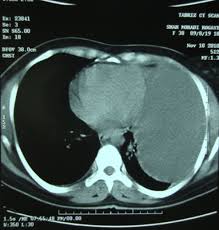

Loculated Pleural Effusion / Solution To Unknown Case 23 Empyema Loculated Pleural Effusion Radiologypics Com / Other causes are complicated parapneumonic effusion , empyema, and tuberculosis.. Jan 22, 2020 · loculated effusions occur most commonly in association with conditions that cause intense pleural inflammation, such as empyema, hemothorax, or tuberculosis. More than one half of these massive pleural effusions are caused by malignancy; Other causes are complicated parapneumonic effusion , empyema, and tuberculosis.

Jan 22, 2020 · loculated effusions occur most commonly in association with conditions that cause intense pleural inflammation, such as empyema, hemothorax, or tuberculosis. More than one half of these massive pleural effusions are caused by malignancy; Other causes are complicated parapneumonic effusion , empyema, and tuberculosis.

Jan 22, 2020 · loculated effusions occur most commonly in association with conditions that cause intense pleural inflammation, such as empyema, hemothorax, or tuberculosis. Other causes are complicated parapneumonic effusion , empyema, and tuberculosis. More than one half of these massive pleural effusions are caused by malignancy;